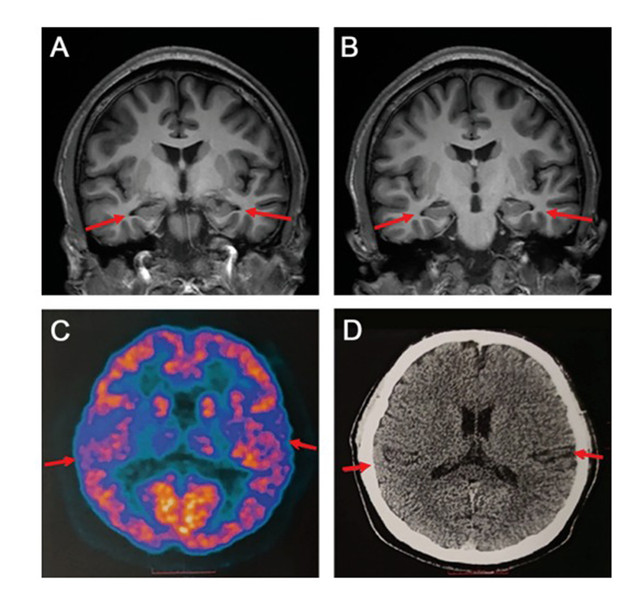

Ảnh minh họa.